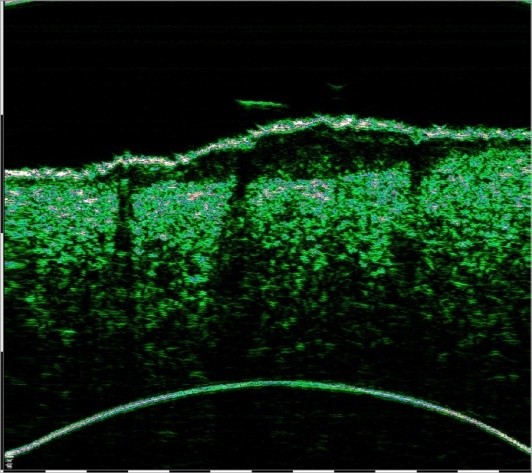

Η εικόνα του δέρματος με Υπέρηχο Υψηλής Συχνότητας (HFUS) στις σαρώσεις είναι οπτικά συγκρίσιμη με την ιστολογική εικόνα. Οι σαρώσεις HFUS έχουν υψηλή ανάλυση και ερμηνεύονται εύκολα από τους ειδικούς. Πολλοί επιστήμονες αναφέρονται στους υπερήχους υψηλής συχνότητας ως βιομικροσκοπία in vivo (σε έμβιο οργανισμό)

Η άμεση ποσοτική μέτρηση όγκων με HFUS προσφέρει μέγιστη αξιοπιστία και αντικειμενικότητα. Ο προσδιορισμός του μεγέθους του όγκου, του βάθους εισβολής του, των ορίων του, καθώς και των ιστών που εμπλέκονται στη νεοπλασματική διαδικασία με HFUS είναι ζωτικής σημασίας λόγω της έλλειψης άλλων διαθέσιμων μη επεμβατικών μεθόδων για την αντικειμενική αξιολόγηση των δομικών αλλαγών στο εσωτερικό του δέρματος.

2.9mm depth , 7.1mm width

Οζώδες Βασικοκυτταρικό Καρκίνωμα. Σάρωση με υπέρηχο υψηλής συχνότητα που δείχνει τις διαστάσεις του όγκου και Βιντεοδερματοσκόπηση.

Η σάρωση υψηλής συχνότητας με τη χρήση αισθητήρων 22 και 75 MHz, επιτρέπει τη χρήση απλών κριτηρίων κακοήθειας για τη διάγνωση όγκων του δέρματος με υπερηχογραφικές ενδείξεις. Τα πιο έντονα κακοήθη χαρακτηριστικά είναι: σχηματισμός με τάση σταθερής ανάπτυξης, ανώμαλα περιθώρια και κατακόρυφος προσανατολισμός ανάπτυξης του όγκου, ο οποίος αναπτύσσεται σε βάθος και έχει ακανόνιστη θολή ετερογένεια, ενώ ταυτόχρονα η αγγείωση και η μικροκυκλοφορία ενισχύονται κατά την απεικόνιση Doppler.

Καλοήθη σημάδια: μακροχρόνιος υφιστάμενος όγκος χωρίς επαρκή ανάπτυξη, με σαφή περιγράμματα και περιθώρια με τους περιβάλλοντες ιστούς, με επιφανειακή θέση στην επιδερμίδα και το άνω χόριο, με κανονική υπό- ή υπερ.-ετερογενή εικόνα και με μη ανιχνεύσιμη ροή αίματος κατά την εξέταση Doppler.

Εάν εντοπιστούν μία ή περισσότερες κακοήθεις εδείξεις, ο όγκος μπορεί πρωτογενώς να ταξινομηθεί ως κακοήθης.

Η βάση της επιτυχημένα επιλεγμένης τακτικής για τη θεραπεία του BCC είναι η σωστή αξιολόγηση της κλινικής του μορφής και της μορφολογίας του. Ο υπέρηχος υψηλής συχνότητας καθιστά δυνατή τη διαφοροποίηση των τύπων BCC: επιφανειακά, οζώδη, σκληροδερμικά και μικροοζώδη.

Τα επιφανειακά BCC στις υπερηχογραφικές σαρώσεις έχουν οριζόντια επιμήκη περιγράμματα με σαφή οριοθέτηση από το υποκείμενο χόριο με υποηχογενή δομή, ενώ τα οζώδη BCC χαρακτηρίζονται από στρογγυλά ή οβάλ περιγράμματα με διάχυτη υπο-ετεροηχογενή δομή και είναι επίσης σαφώς οριοθετημένα από τους περιβάλλοντες ιστούς. Συχνά οι κουκκίδες που μοιάζουν με εγκλείσματα εμφανίζονται στο κέντρο του όγκου και στην περιφέρεια.

Τα σκληροδερμικά BCC απεικονίζονται ως υποηχογενείς σχηματισμοί με ανομοιόμορφα περιγράμματα, που διεισδύουν βαθιά στο χόριο, με κυματιστά ασαφή όρια.

Βάθος δερματικών όγκων, εσωτερικά όρια και ποσοτική αξιολόγηση της αιματικής ροής

Η HFUS είναι η μόνη διαθέσιμη μέθοδος για τον in vivo προσδιορισμό του μεγέθους του όγκου, του βάθους διείσδυσης, του χαρακτήρα των ορίων και των ιστών που εμπλέκονται στη διαδικασία του νεοπλάσματος.

Αυτές οι κλινικές πληροφορίες είναι ζωτικής σημασίας για τον προεγχειρητικό σχεδιασμό της πλήρους εκτομής του όγκου με σαφή όρια και την αποφυγή υποτροπών μετά την επέμβαση.

Εικόνα: Οζώδες BCC (Βασικοκυτταρικό Καρκίνωμα).

Υπερηχογράφημα υψηλής συχνότητας με μεγέθη όγκων και βιντεοδερματοσκόπηση.